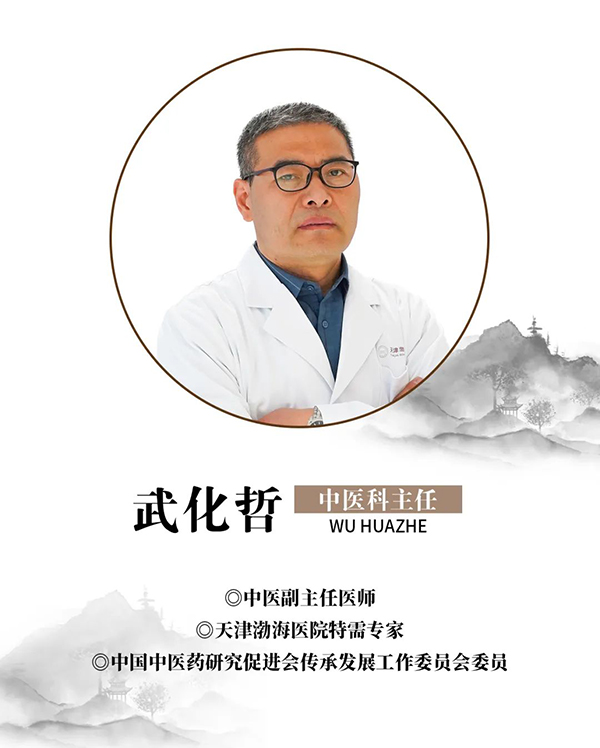

今天我们邀请到中国中医药研究促进会传承发展工作委员会委员,天津渤海医院特需专家,中医杂病专家武化哲主任与大家来聊一聊肺炎。

名医简介

专家介绍

从事临床工作近30年,熟读经典,博览群书,曾跟随国医大师唐祖宣学习,对其用益气活血法治疗脉管炎颇有心得。在国家级期刊发表论文10余篇,善于运用体质辨证及六经辨证进行辨证论治。拥有丰富的临床经验,秉承传统中医理论,运用中西医结合方法诊疗受到了良好效果。

专家擅长

擅长经方治疗鼻炎,哮喘,支气管炎,急慢性胆囊炎,胆结石,慢性胃炎,胃溃疡,十二指肠溃疡,结肠炎,痤疮,湿疹,银屑病,高血压,冠心病,泌尿系结石,前列腺炎,肺结节,甲状腺结节。擅长运用已故名老中医李可老先生的“攻癌夺命汤”化裁加减治疗肿瘤:恶性淋巴瘤,胃癌,食道癌,肝癌,甲状腺癌,骨瘤,宫颈癌,肾癌,膀胱癌等。不仅可以有效提高患者生活质量,还可延长患者生存时间!